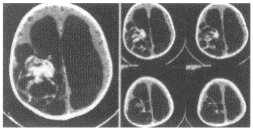

- [材料题] 男性,2岁,正常足月分娩,自1岁后头逐渐增大,颅内压增高,PE:双下肢肌张力增强。

- 简答题2、患者行CT检查图像如下:结合病史,首先考虑患者患何种病?依据是什么?